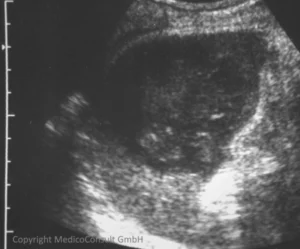

Milzabszess

![]() Ein rundlicher, strukturarmer Bezirk mit einzelnen stärkeren Binenreflexen in der Milz kann auf einen Abszess mit Detritus hinweisen. In diesem Fall haben sich in der linken Flanke allmählich zunehmende Schmerzen entwickelt, die später atemabhängig wurden. Die Atemabhängigkeit deutet auf eine fibrinöse Ausschwitzung auf der Milzoberfläche hin (Perisplenitis). → Abszess |